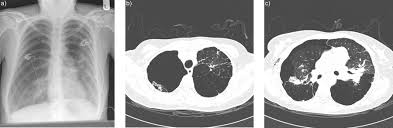

Bullous lung disease symptoms. There are several subtypes of emphysema including subcutaneous emphysema bullous. Group B GOLD 1 or 2. Most people with bullous emphysema experience shortness of breath wheezing coughing up phlegm and centralized pain in their chests especially when engaging in physical activity.

This emphysema also includes deterioration of alveolar tissue and this is basically lung tissue that makes up the walls between air sacs. Bullous Lung Disease is the most common form of emphysema. As the disease gets worse scars form and the tissue becomes stiff and thick.

Some patients suffer from nausea loss of appetite and fatigue as a. Patients frequently present with nonspecific symptoms including intermittent wheeze and cough and these are often attributed to other conditions such as asthma and smoking-related COPD especially when there is concurrent heavy smoking history. As the disease progresses you may find it increasingly difficult to breathe and engage in daily activity.

Emphysematous bullae can cause many respiratory problems including shortness of breath. Your FEV 1 is between 50 and 80. The harmful effects of tobacco smoking especially with regard to the aetiology of chronic obstructive pulmonary disease are well documented3 Large emphysematous bullae may develop usually in the context of significant tobacco exposure over many years and tend to be associated with airway obstruction reduced gas transfer factor and diffusion coefficient and evidence of centrilobular.

This is condition which is characterized by abnormal and enlarged air spaces within the lungs.